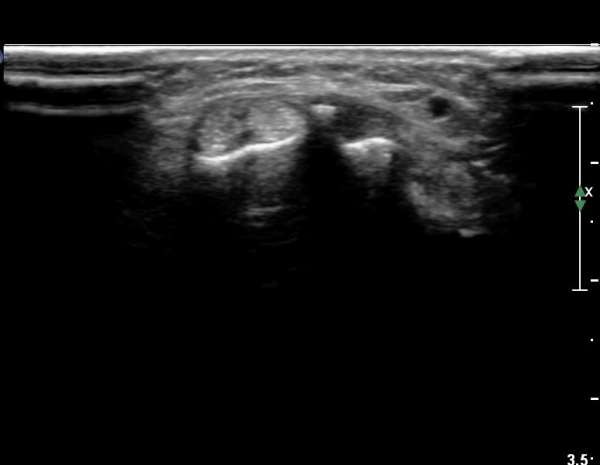

ŽÃËÀÚ¸¦ Á¶±Ý ´õ ¸»´ÜÀ¸·Î À̵¿ÇÏ´Ï Àå, ´Ü¿äÃø¼ö±Ù½ÅÀü°ÇÀÌ ºÐ¸®µÇ¾î °üÂûµÇ°í °ÇÀÇ ºÎÁ¾°ú

°Ç ÁÖÀ§ ¼ö¾×Àú·ù°¡ °üÂûµÈ´Ù(»çÁø 7, 8).